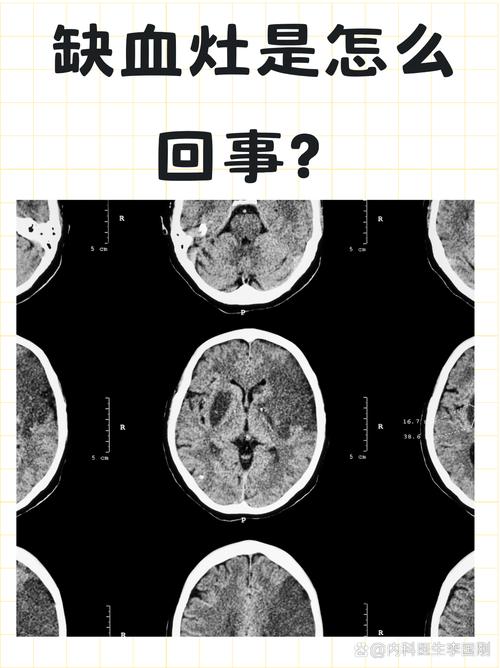

什么是脑点状缺血灶?

“脑点状缺血灶”,在医学影像报告上也可能被称为:

- 缺血性腔隙灶

- 腔隙性脑梗塞(这是一个更严重的说法,但通常指很小的梗塞)

- 脑白质变性

- 脑小血管病

本质: 它是由于大脑深部的微小血管(直径小于1.5-2毫米)发生堵塞或缺血,导致该血管供应的一小块脑组织(像一个“小点”一样)发生缺血、坏死,最终形成一个小小的疤痕或软化灶。